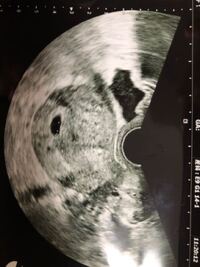

妊娠5週1日(5w1d)の赤ちゃんのエコー写真です。投稿も募集しています。 その日は本当に小さい影でこれかどうか、まだわからないと言われました。出血痕かもね、と。 前回胎嚢見えてすぐの流産、今回は早くに胎嚢確認できて、順調そうとの事 7 週 胎芽 見え ない 🤫 妊娠5週~7週 胎芽見えない 胎嚢が確認できる時期はいつ? See full list on uptoyoume 胎嚢と胎芽確認できる時期はいつごろ? 見えない時の原因など|大 1胎嚢(たいの 5週だと、健康で問題ない胎児の場合でも、稀に胎嚢が小さく見えない妊娠検査薬で陽性だったけど、病院へ行くと 「胎嚢が見えない」 、 「胎嚢はあるけど胎芽が確認できない」 といわれた。 胎嚢は早ければ妊娠4週のはじめに確認でき、一般的には 妊娠4週末から妊娠5週頃 までに見えます。 続いて胎芽・心拍が妊娠8週までに全ての妊婦さんに確認できると

妊娠5週5日(週数ほぼ正確)胎嚢確認日。 hcg 1434 だが、胎嚢確認できず。 胎嚢が見えない原因、3つの可能性 胎嚢まだが発育してなくて見えていない状態; 妊娠6週で胎嚢が見えない、7週でも心拍が確認できなかった話 nishinojyou 21年5月30日 / 22年2月28日 娘を妊娠したときのお話です タイトル通り、 娘ちゃんは胎嚢確認も、心拍確認も遅くてとても不安でした 暇さえあればネットサーフィンの毎日1 妊娠5週を過ぎると子宮内に胎嚢 ( GS ) が見えます。見えない場合 a 排卵日が遅れて妊娠成立 ( 5週を過ぎていない ) b 胎嚢が見えない間に成長が止まってしまった ( 化学的流産 ) c 異所性妊娠 の鑑別をしていきます。